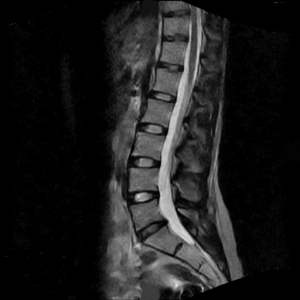

What is an MRI?

MRI or Magnetic Resonance Imaging, is a type of powerful radiographic study that provides a clear diagnostic picture without using radiation. The MRI image gives enhanced views of the body part in question. An MRI scan of the spine, for example, provides a superior view of the discs in the back, as well as the nerves and other soft tissues.

The doctor can look at the MRI films and determine whether there is a pinched nerve, a degenerative disc, a tumor, or in some cases spinal stenosis. The doctor may use the MRI to correlate with the patient's symptoms and physical exam. The greatest advantage of the MRI is in its ability to allow the physician to see inside the body without the need for surgery or potentially harmful radiation.